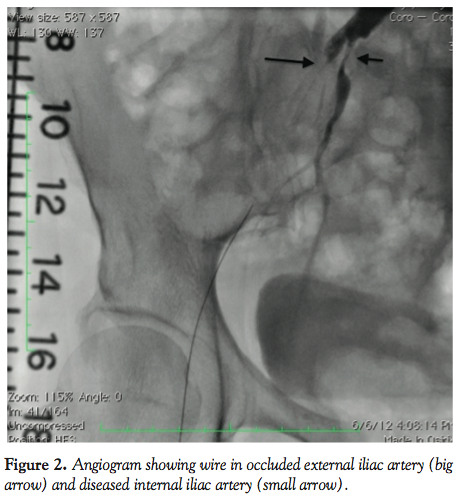

After left to right crossover with a 6 x 45 cm sheath, a Confianza wire (Abbott Vascular) was used to cross the CTO of EIA and a Fox SV 5.0 x 40 mm balloon (Abbott Vascular) was used for balloon angioplasty (BA) of the lesion. During and after BA, the patient experienced severe pain in the hip, right groin, and genital area. Repeat images showed compromised flow in the right IIA (Figure 3). There was no evidence for a perforation at the side of the pain, abdomen was soft and there was no tenderness or change in pain with deep palpation of the right groin. Then, a Prowater wire (Abbott Vascular) was advanced in the right internal iliac artery and a Fox SV 5.0 x 40 mm balloon (Abbott Vascular) was inflated at 4 atm with establishment of normal flow in the vessel with less than 20% residual and immediate